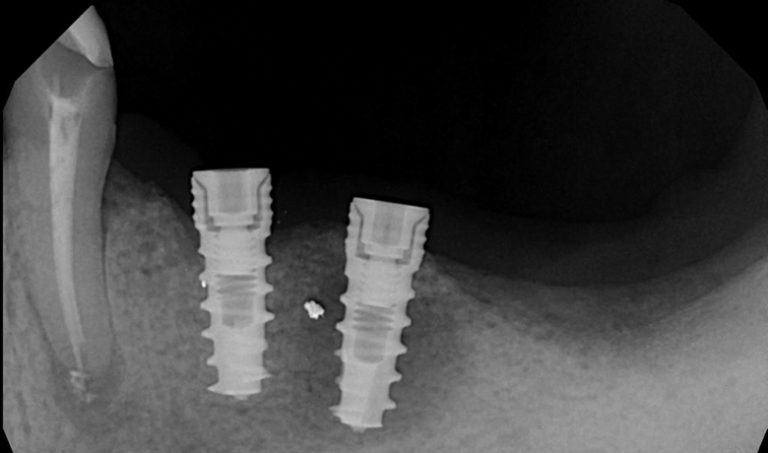

- 3D-снимок: врач смотрит на состояние костной ткани.

- Зондирование: таким образом доктор определяет глубину зубодесневого кармана и индекс кровоточивости.

- Степень подвижности искусственного корня.